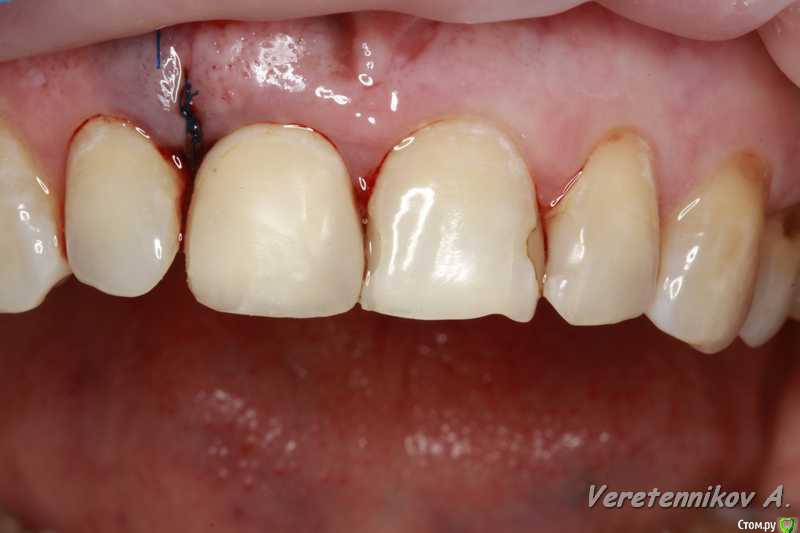

Популярный пост an_ver Опубликовано 15 января, 2016 Популярный пост Поделиться Опубликовано 15 января, 2016 11,жил долго и счастливо..но тут Новый год(((, скол ниже уровня ЦЭС на 3 мм...от экструзии отказалась.Из своего зуба сколхозил шаблон,чтоб наверняка. Удалил,кюретаж,вестибулярка целая, SPI 4.2*13 мм,с бугра ССТ,на всякий)),в щели Апатос,врем.абатмент,врем.коронка из своего зуба. 1ч.20мин.)) 27 Ссылка на комментарий

an_ver Опубликовано 16 января, 2016 Автор Поделиться Опубликовано 16 января, 2016 (изменено) в щели апатос,сст в сформированный карман! Андрей красиво и все по пунктам,как так вышло что сосочек порвался?может не стоило так глубоко сст заводить?Чесно,фиг знает((( тока счас обратил внимание,наверно 15С орудовал глубоко (набор Деплер для туннеля в клаве был),((( немного лоскут перфорнул...если кто заметил,решил глубже завести ластик сст Изменено 16 января, 2016 пользователем an_ver Ссылка на комментарий

an_ver Опубликовано 16 января, 2016 Автор Поделиться Опубликовано 16 января, 2016 перфо не заметил,но понял теперь почему так глубоко сст!ждем динамики!Перфо-второй шов,ниже Ссылка на комментарий